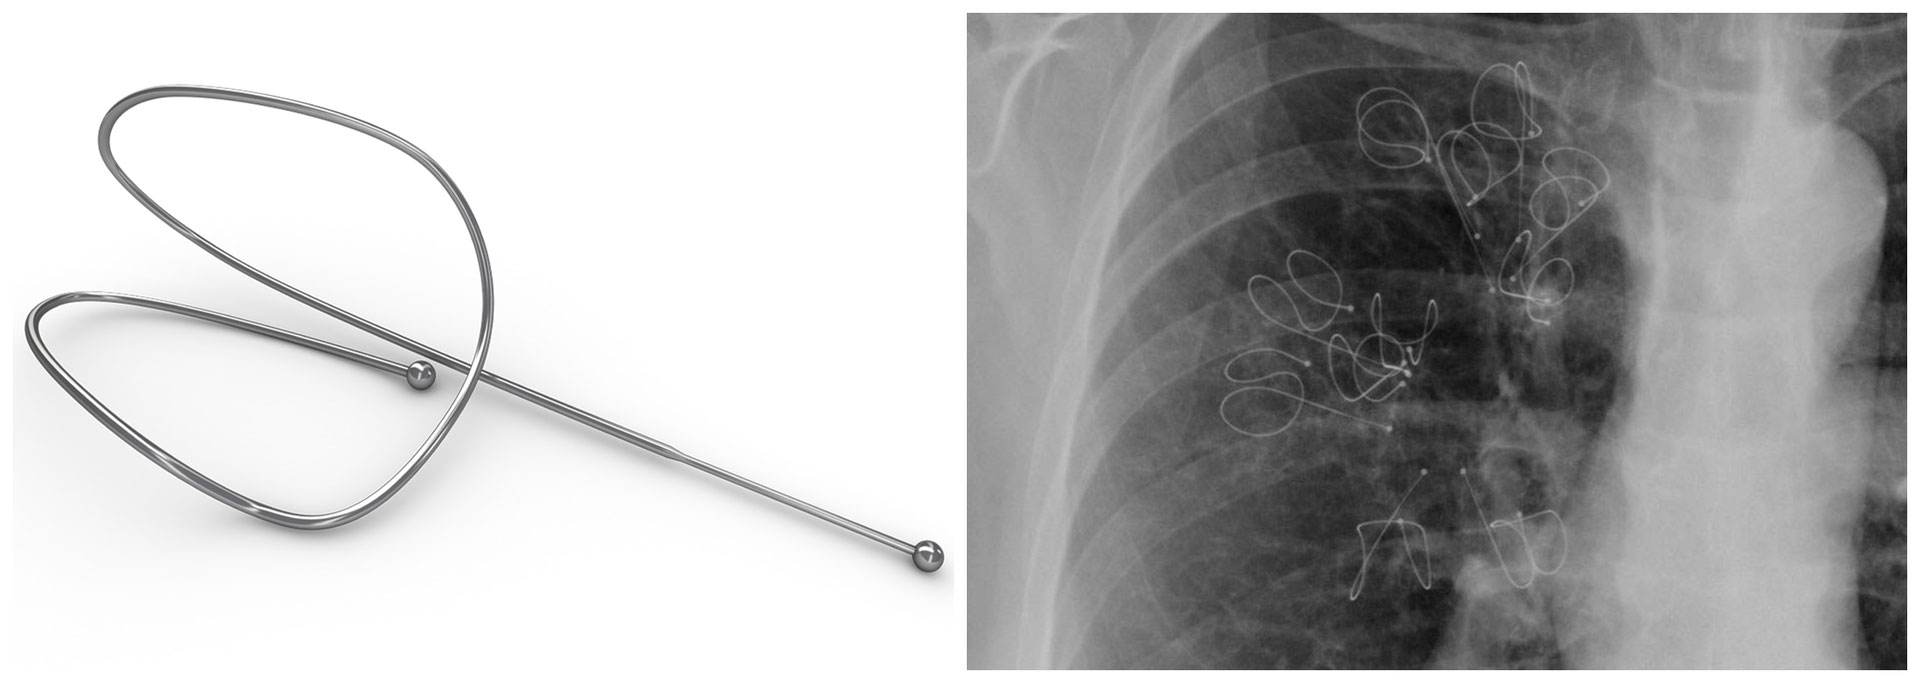

Components of the RePneu Lung Volume Reduction Coil System. Download Coils In Lungs Lung volume reduction using nitinol coils is a bronchoscopic intervention inducing regional parenchymal volume reduction and. We report the medium term effectiveness. The lung volume reduction coil treatment is a minimally invasive bronchoscopic treatment option for emphysema patients who suffer from. The lung volume reduction coil treatment is a minimally invasive bronchoscopic treatment option for emphysema patients who. The pathophysiological. Coils In Lungs.

From www.researchgate.net

The PneumRx endobronchial coil system. The system consists of a Coils In Lungs The lung volume reduction coil treatment is a minimally invasive bronchoscopic treatment option for emphysema patients who. The pathophysiological mechanism involved in coil treatment appears to be the improvement in lung mechanics due to the. The lung volume reduction coil treatment is a minimally invasive bronchoscopic treatment option for emphysema patients who suffer from. Lung volume reduction using nitinol coils. Coils In Lungs.